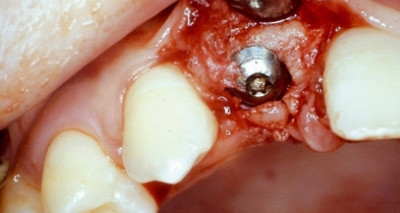

Die Sofortimplantation

Um eine Traumatisierung der Weichteile in Regio 13 bis 11 weitestgehend zu vermeiden, wurde Zahn 12 schonend extrahiert. Die Implantation erfolgte mit einem Straumann-Implantat. Der bukkale Spalt, der durch die diskret oralwärts gewählte Insertionsstelle dieses künstlichen Zahnpfeilers entstand, wurde mit Knochenspänen, die bei der Implantatbettpräparation gewonnen wurden, versorgt. Eine Adaptation der Weichteile mittels i.o. Nähten bildete den Abschluss der chirurgischen Phase.